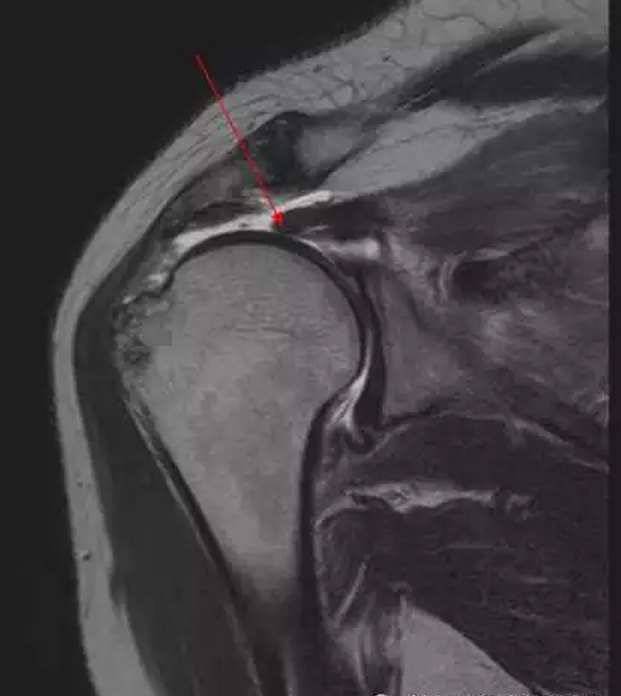

2 肩关节mri一个层面显示肩袖肌腱(冈上肌腱)撕裂

95%肩袖损伤由肩峰撞击所致,而冈上肌腱是最易受损的部位,下面的mri